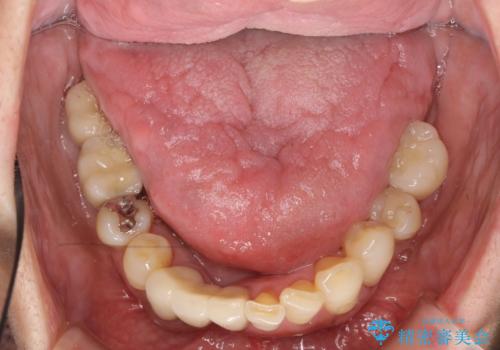

歯周病 インプラントによる咬合機能回復

- 歯が全体的にグラグラし、しっかりと物が噛めなくなり歯周病治療を希望され来院されました。

残すことのできる歯、残すことのできない歯を初期治療を進めながら見極め、最終的に臼歯部はインプラント、上顎前歯は入れ歯による補綴計画となりました。